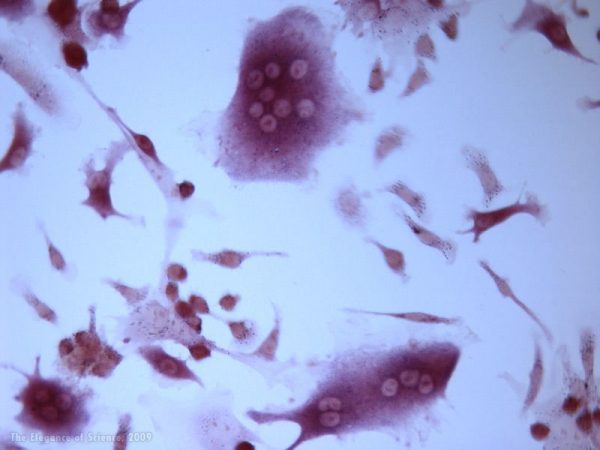

Fatal Attraction, Yaima Luzardo, Clayton E. Mathews, & Molecular Pathology Core